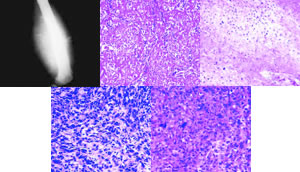

图1 骨肉瘤X线片

股骨远端侧位平片示一个巨大的骨外高密度肿块,以及“日光放射状”骨膜反应。

图2 成骨肉瘤镜下观

(HE染色,×100)

以细胞外骨基质为主,有不成熟骨沉积形成

图3 软骨肉瘤镜下观

以透明软骨细胞为主,但右上方可见少量类骨质形成

图4 纤维肉瘤镜下观

(HE染色,×250)

以类似不典型成纤维细胞的梭形细胞为主

图5 恶性纤维组织细胞瘤镜下观(HE染色,×250)

肿瘤细胞可表现为纤维组织细胞样或上皮细胞样, http://www.100md.com